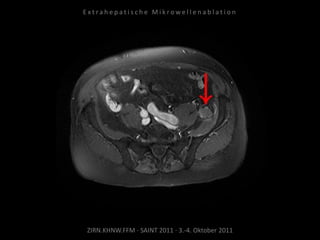

Kontrollbildgebung:

MRT 10.09.2010